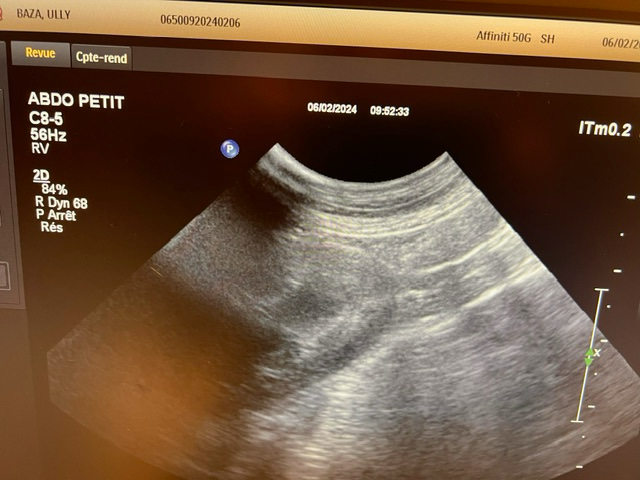

강아지가 목줄을 하고 산책 중에 갑자기 집에 가려고 차도로 뛰어드는바람에 교통사고가 났습니다. 천천히 달려오는 차에 부딪히기는 했지만 걱정돼서 바로 병원으로 갔고 엑스레이, 초음파, 혈액검사 다 시행했지만 이상이 없다고 얘기했습니다. 그런데 사고 이후로 계속 토를 해서 병원에 가서 구토약이랑 진통제를 받아와서 먹였는데도 계속 구토를 하네요ㅠ 사료를 그대로 토하는데 이게 스트레스때문인지 아니면 검사상에 이상이 있는지 여쭤보고 싶어서 글 남깁니다. 또한 가슴쪽을 부딪혔는데 흉부 엑스레이 상에서 이상소견이 있는지 확인 좀 부탁드립니다.

초음파 검사의 경우 초음파를 직접 본 사람이 아니면 찍어놓은 사진으로는 아무런 판단을 할 수 없고 해서도 안됩니다.

주치의의 판단이 가장 정확한 판단이겠으나 지현형으로 장기 손상이 일어나는 경우가 종종 있기 때문에 증상이 지속된다면 복부 초음파 검사를 다시 받아볼 필요가 있어 보입니다.